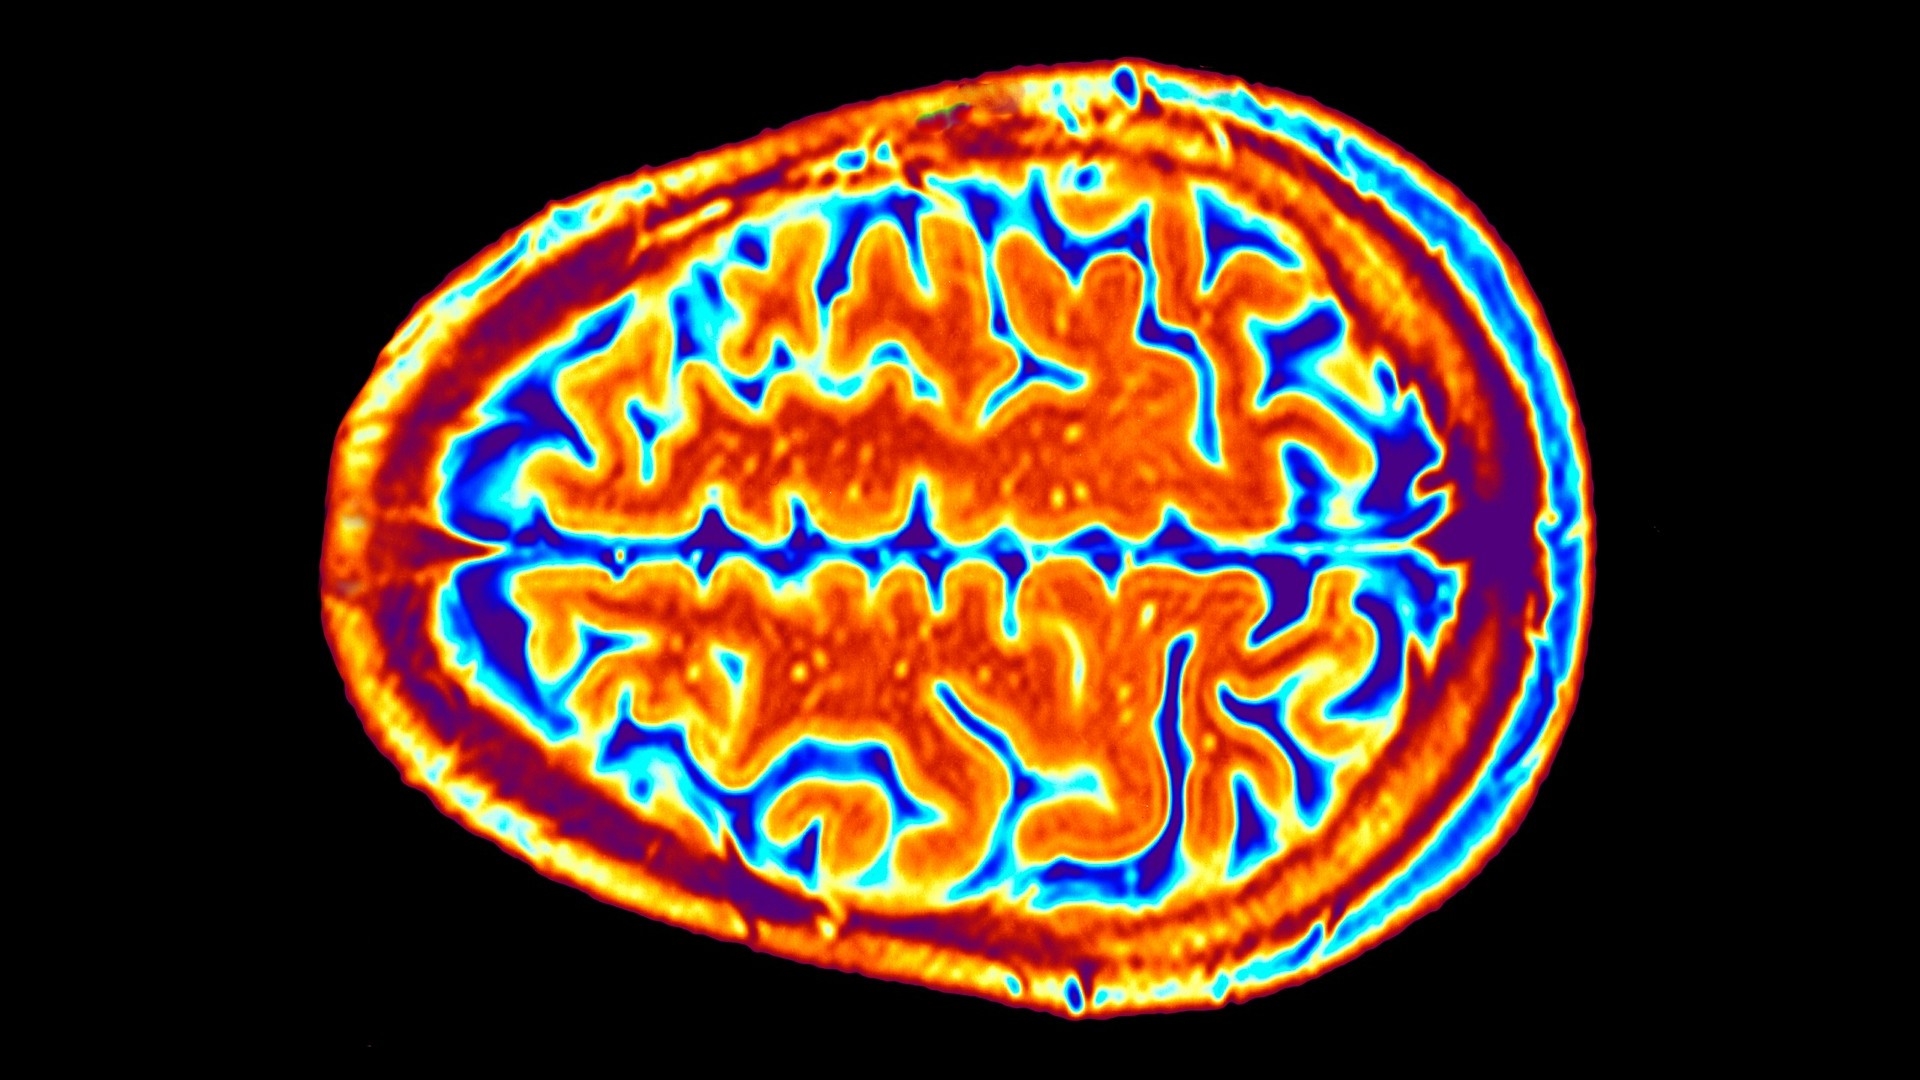

Whether it’s a PET scan or an fMRI, brain activity scans are fascinating tools used in the field of neuroscience. But when it comes to crossword puzzles, they can be a bit tricky to decipher. Let’s dive into some tips to crack that brain activity scan crossword clue!